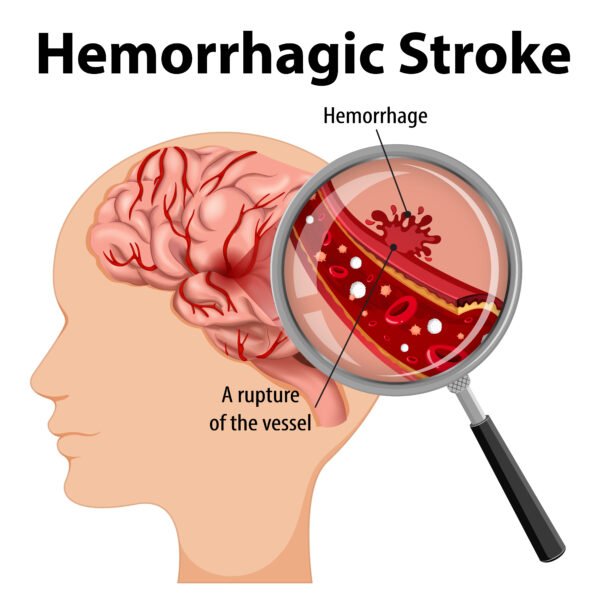

- Stroke